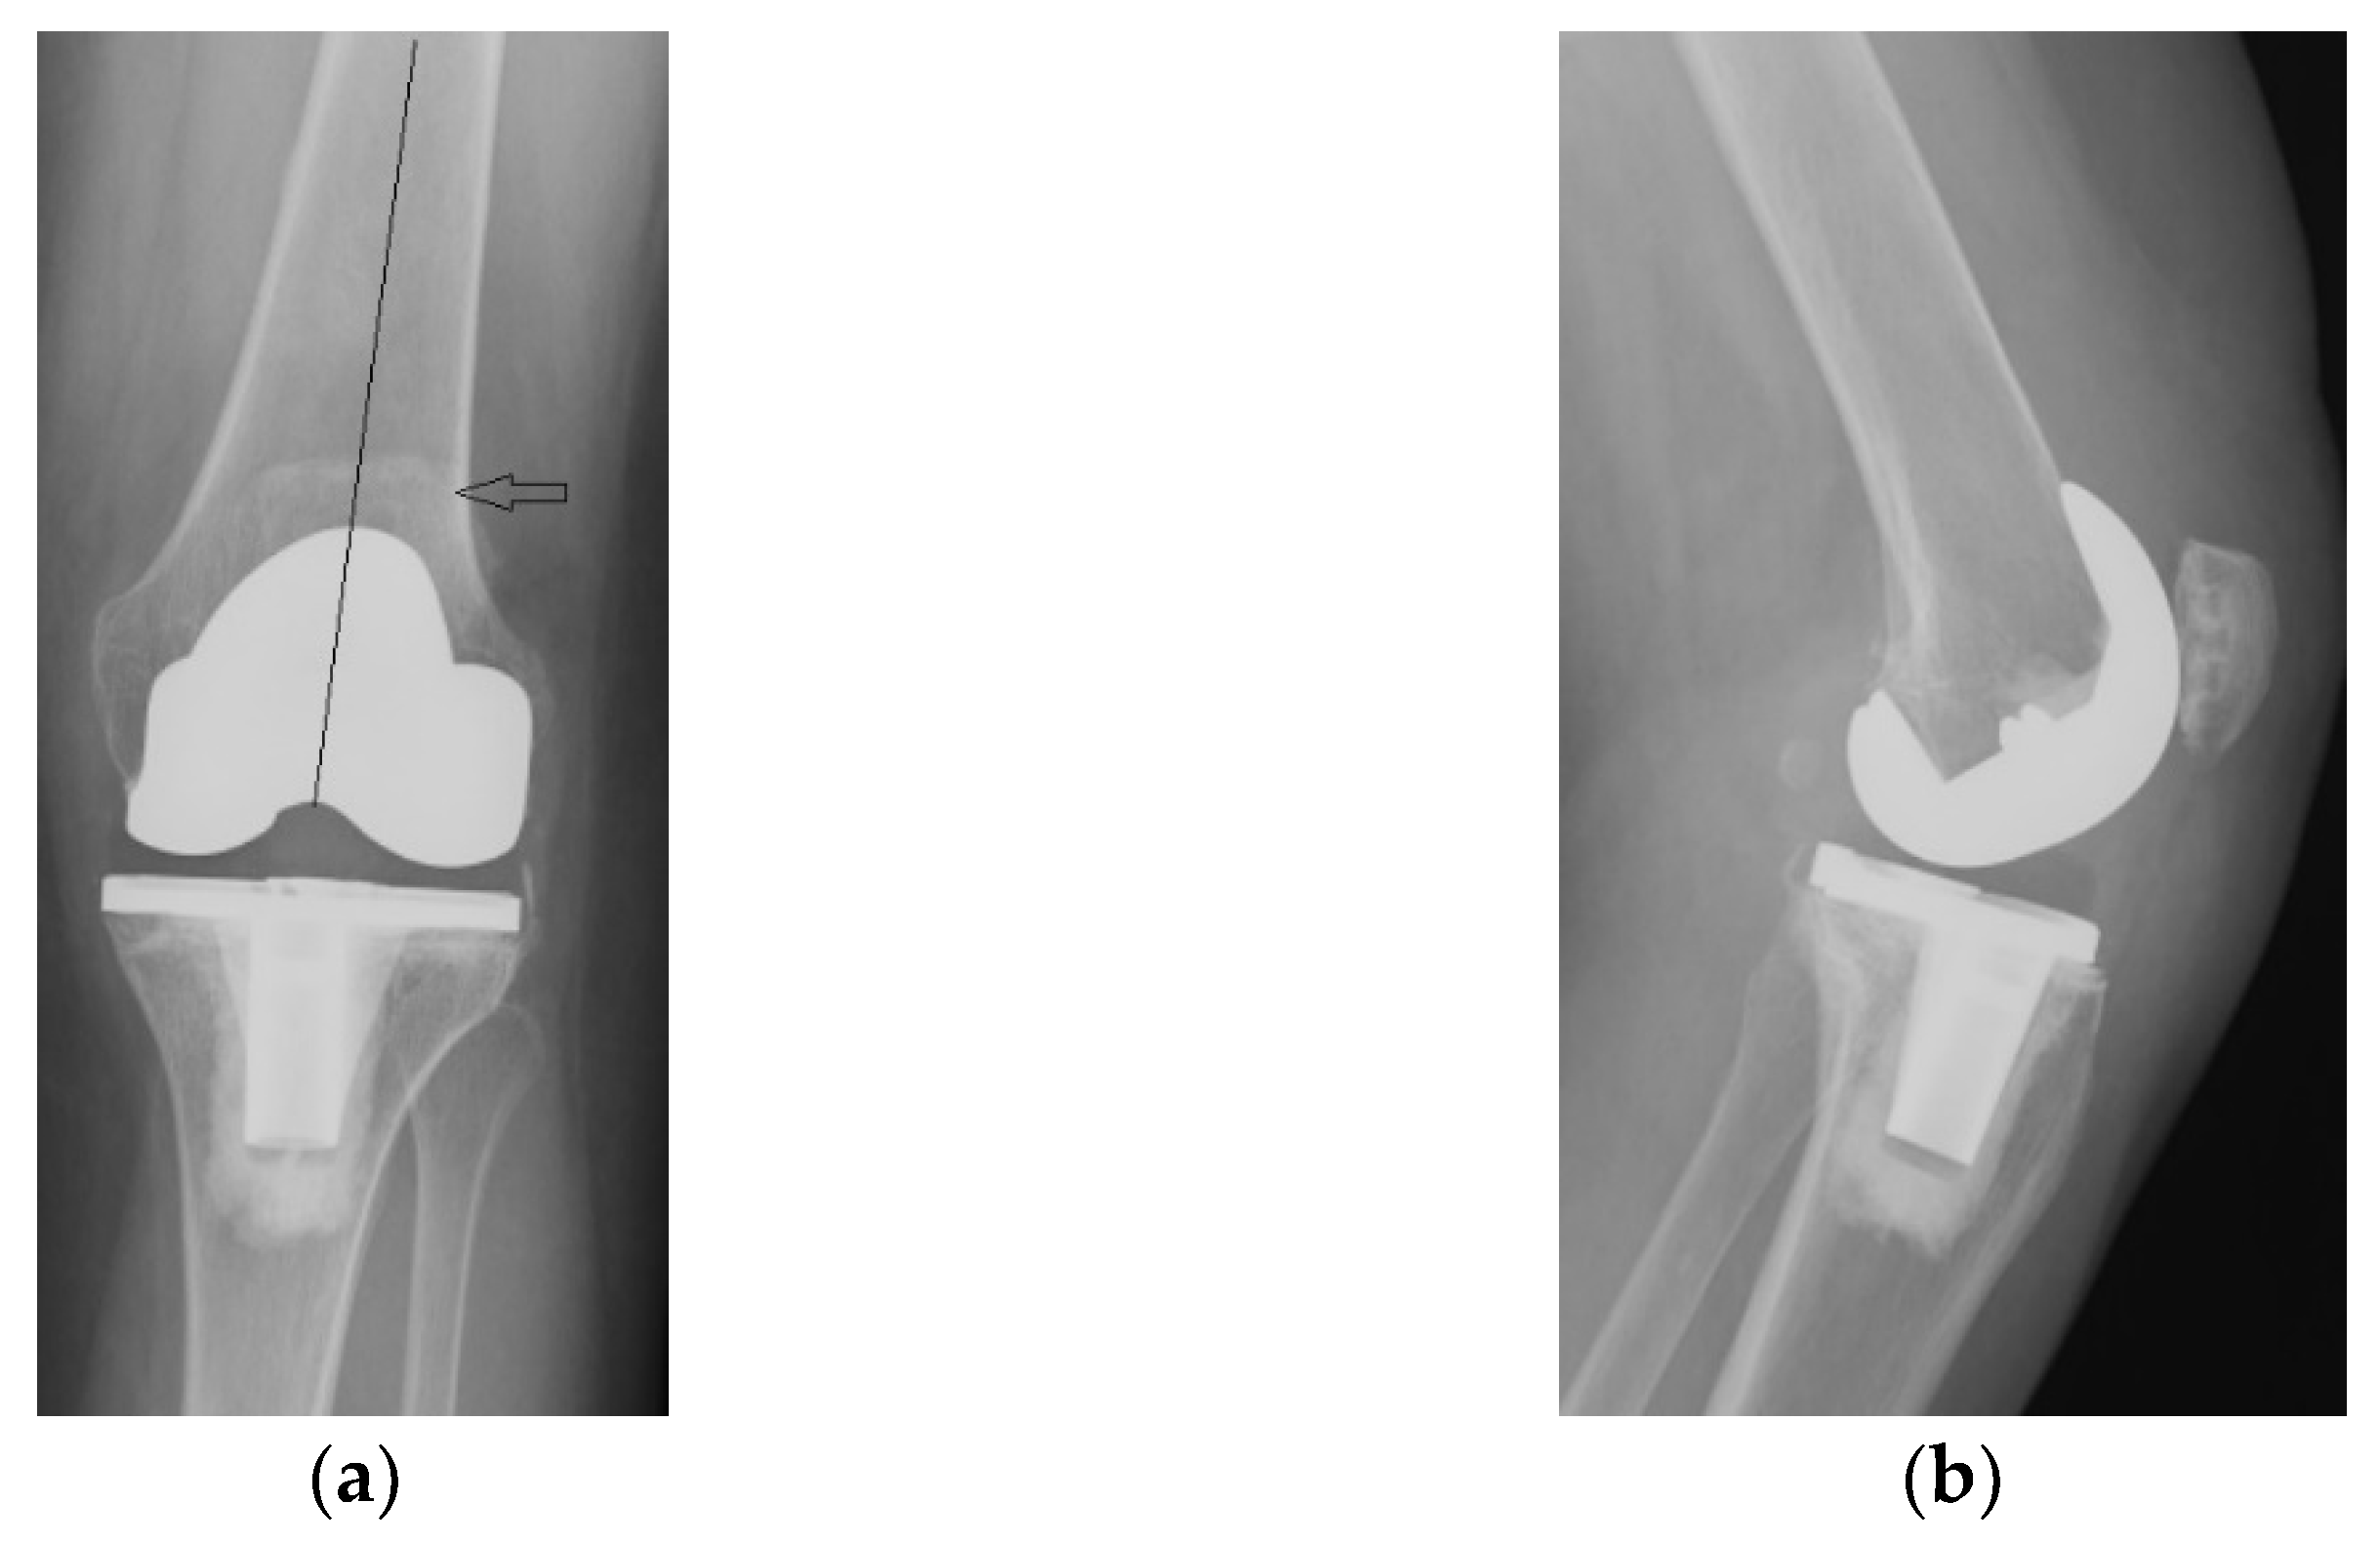

The immediate and distant postoperative evolution were favorable, as the radiological evaluation performed on the 2nd day after surgery shows; unfortunately, the lateral view is rotated (Figure 6).

Figure 6.

(a) Coronal view, patella centered on femoral axis (arrow); (b) Lateral view.

Radiological and clinical follow-up were performed at 6 weeks, 3 months and then 12 months after surgery (Figure 7, Figure 8 and Figure 9).

Figure 7.

Radiological imaging at 6 weeks after surgery: (a) Coronal view; (b) Lateral view.

Figure 8.

Radiological imaging at 3 months after surgery. (a) Coronal view, patella is centered to the femoral component (arrow); (b) lateral view.